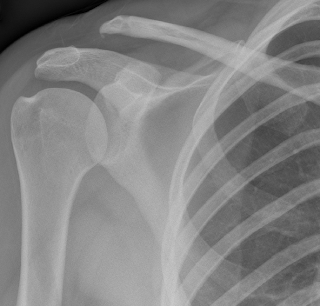

Normal AC joint (The Joint between the end of collar bone and shoulder blade)

The joint between the outer end of the collar bone (clavicle) and shoulder blade (scapula) is called the acromioclavicular joint.

X ray of Normal AC joint